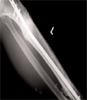

Pre

Op

Open fracture tibia treated with external fixator and developed chronic osteomyelitis